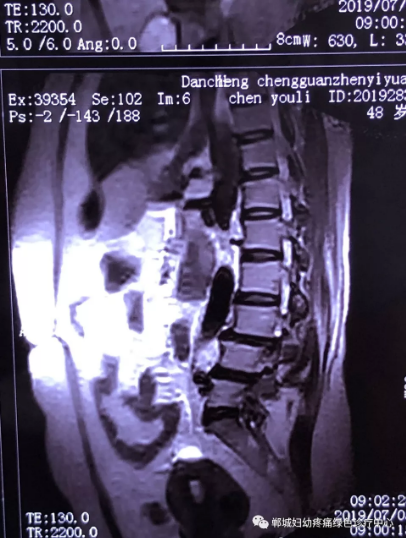

2年前,雙樓鄉(xiāng)的陳女士不小心摔了一跤后出現(xiàn)腰痛,當時到藥店買了膏藥來貼,疼痛減輕了一些,但是從此以后反反復復出現(xiàn)腰痛。到處進行治療,不見好轉,最近腰痛加重了,痛得受不了,出現(xiàn)行走后甚至持續(xù)的雙下肢后側或后外側放射性的疼痛麻木、間歇性跛行等癥狀。陳女士趕忙去醫(yī)院治療,做了磁共振檢查后確診為腰椎滑脫、腰椎反弓。醫(yī)生都告訴她需要手術治療。隨后她又帶著片子咨詢了好幾家醫(yī)院,結果都是一樣,她已經做好了手術的打算。

治療前

不經意間聽到有人說醫(yī)院疼痛科可以不吃藥不打針,用無痛苦、無創(chuàng)傷的方法治療腰痛。陳女士就抱著試試看的心理來到了鄲城縣婦幼保健院疼痛科,疼痛科時慶祥主任詳細了解病情,結合腰椎磁共振及體征后告訴陳女士她不用手術,通過腰椎脊柱定位周期減壓牽引系統(tǒng)(外星艙)也能解決腰痛、腰椎滑脫、腰椎反弓這些問題。陳女士未曾想到經過十五天的治療后腰部及下肢放射性疼痛癥狀基本消失。陳女士感到十分激動與感謝,就在當?shù)匦l(wèi)生院做了一個腰椎正側位x片和之前的片子作對比,發(fā)現(xiàn)腰椎滑脫明顯改善。她說道:感謝鄲城縣婦幼保健院疼痛科的所有醫(yī)護人員、感謝外星艙脊柱減壓治好了我的腰痛,也感謝告訴我來這里的人,她的一句話,讓我省了好幾萬元的手術費!